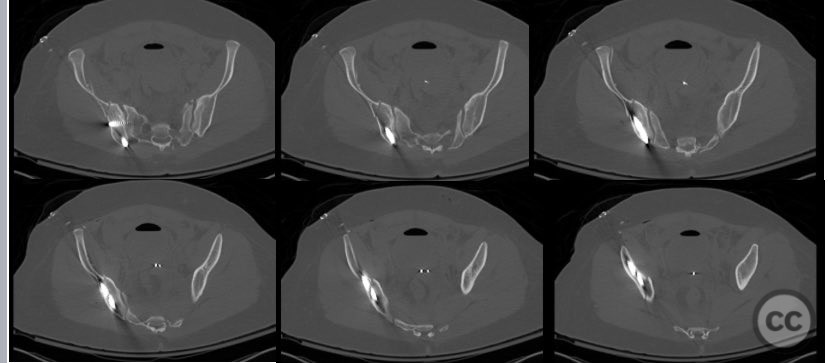

Clinical and radiological findings:  A 26-year-old female sustained a closed pelvic ring injury following a motor vehicle accident. She was hemodynamically stable, neurologically intact, and had no other associated injuries. Skin integrity was preserved. Initial management included pelvic binder application and 10 pounds of distal femoral skeletal traction. Portable AP pelvic radiograph demonstrated a left-sided sacral fracture with associated ipsilateral iliac wing and pubic ramus fractures, consistent with an AO/OTA 61-B2 (lateral compression type II) injury pattern.

Planning remarks:  The preoperative plan included supine positioning with maintenance of skeletal traction. The left sacral fracture was to be stabilized first with percutaneous iliosacral screw fixation. An anterior iliac approach was planned for direct reduction and fixation of the iliac wing fracture, followed by medullary screw fixation of the iliac crest and pelvic brim. Intraoperative fluoroscopic stress testing of the left pubic ramus fracture and overall pelvic ring stability was planned.

Anatomical surgical approach:  The left sacral fracture was addressed first via percutaneous placement of iliosacral screws under fluoroscopic guidance. An anterior approach to the iliac wing was performed via a longitudinal incision along the crista iliaca, subperiosteal dissection to expose the fractura alae ossis ilii, followed by debridement, reduction, and temporary clamping. Definitive fixation was achieved with two 7mm diameter cannulated fully threaded medullary screws placed across the iliac crest and pelvic brim into the corpus ossis ilii. The left ramus ossis pubis fracture and overall cingulum pelvicum were assessed intraoperatively with fluoroscopy for residual instability.